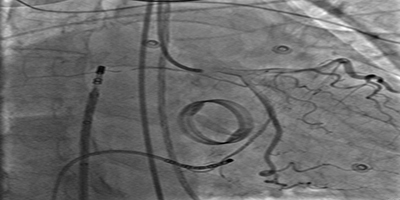

Coronary Sinus Stenting to Enable Left Ventricular Lead Implantation During Cardiac Resynchronization Therapy: A Case Report